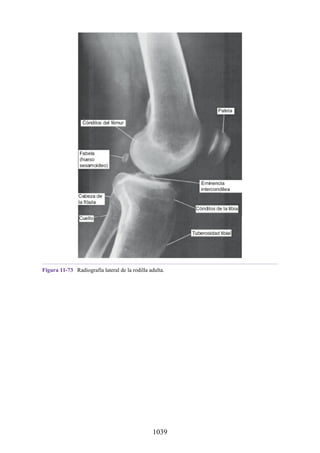

en la figura 1-11 se resumen los tipos de articulaciones sinoviales. Los ejemplos

proporcionados no necesariamente incluyen todos los tipos de articulaciones.